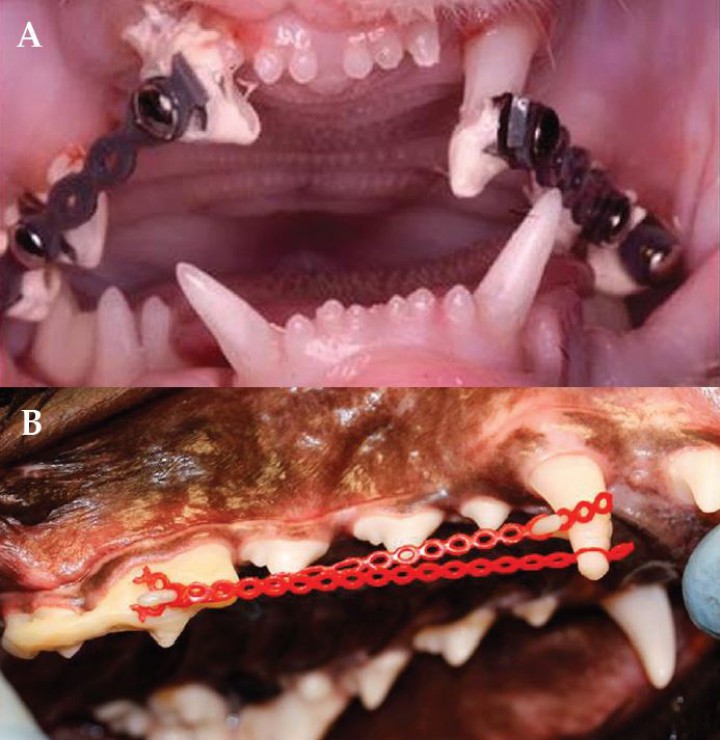

Mesioversión de los caninos maxilares o “Diente en lanza”

Es una maloclusión clase 1,[ Angle EH. Treatment of malocclusion of the teeth and fractures of the maxillae. Angle’s System. S White Manufacturing Co, Philadelphia. 1900; 34-44; 192-232. ] en la cual el canino maxilar está desplazado rostralmente,[ Harvey CE, Emily PP. Small Animal Dentistry, Mosby, St.Louis. 1993. , Shipp AD, Fahrenkrug P. Practicioner’s Guide to Veterinary Dentistry. Dr. Shipps Laboratories, Beverly Hills. 1992; 122-123. ] pudiendo entrar en contacto con el tercer incisivo del mismo cuadrante (Fig. 6). Generalmente, el canino está infraerupcionado, y puede estar asociado a la persistencia del canino de leche.

<p>Mesioversión de ambos caninos maxilares en un gato.</p>

Mesioversión de ambos caninos maxilares en un gato.

Se ha descrito la existencia de predisposición genética en determinadas razas, como el Pastor de Shetland, Scottish Terrier, Galgo Italiano y gatos de raza Persa.[ Brook AN. Pathology in the pediatric patient. En: Niemiec B: Small Animal Dental, Oral and Maxillofacial Disease. Manson Publishing. London 2010; 90-123. , Harvey CE, Emily PP. Small Animal Dentistry, Mosby, St.Louis. 1993. , Shipp AD, Fahrenkrug P. Practicioner’s Guide to Veterinary Dentistry. Dr. Shipps Laboratories, Beverly Hills. 1992; 122-123. ]

La etiología es múltiple, pudiendo deberse a enfermedades sistémicas y endocrinas, neoplasias, formaciones quísticas, o a la presión que ejercen el labio, la lengua o la mejilla durante el desarrollo.[ Brook AN. Pathology in the pediatric patient. En: Niemiec B: Small Animal Dental, Oral and Maxillofacial Disease. Manson Publishing. London 2010; 90-123. , Shipp AD, Fahrenkrug P. Practicioner’s Guide to Veterinary Dentistry. Dr. Shipps Laboratories, Beverly Hills. 1992; 122-123. ] El diente en lanza, a menudo se diagnostica como hallazgo ocasional a los seis meses de edad, cuando se anestesia al animal para realizar su esterilización.[ Brook AN. Pathology in the pediatric patient. En: Niemiec B: Small Animal Dental, Oral and Maxillofacial Disease. Manson Publishing. London 2010; 90-123. ] Es importante realizar una buena exploración oral, ya que esta desviación predispone a la enfermedad periodontal. Además, si se produce el contacto con el tercer incisivo, el canino mandibular se desplazará labialmente pudiendo ocasionar ulceras labiales.[ Brook AN. Pathology in the pediatric patient. En: Niemiec B: Small Animal Dental, Oral and Maxillofacial Disease. Manson Publishing. London 2010; 90-123. , Harvey CE, Emily PP. Small Animal Dentistry, Mosby, St.Louis. 1993. ]

Ortodoncia

Se trata de una terapia larga que puede resultar difícil. Se utilizan botones ortodónticos y gomas elásticas.[ Brook AN. Pathology in the pediatric patient. En: Niemiec B: Small Animal Dental, Oral and Maxillofacial Disease. Manson Publishing. London 2010; 90-123. , Harvey CE, Emily PP. Small Animal Dentistry, Mosby, St.Louis. 1993. , Wiggs RB, Lobprise HB. Veterinary Dentistry, Principles and Practice. Lippincott-Raven, Philadelphia. 1997; 130; 440-444; 472-474 . ] Los botones se unen al canino maxilar y la unión distal es, generalmente, al cuarto premolar o al primer molar maxilares, siendo necesaria la ausencia de patología radicular para asegurar un buen anclaje[ Brook AN. Pathology in the pediatric patient. En: Niemiec B: Small Animal Dental, Oral and Maxillofacial Disease. Manson Publishing. London 2010; 90-123. , Wiggs RB, Lobprise HB. Veterinary Dentistry, Principles and Practice. Lippincott-Raven, Philadelphia. 1997; 130; 440-444; 472-474 . ] (Fig. 7). En la mayoría de los casos el paciente debe llevar un dispositivo de “levante de mordida” que la eleva hasta que el diente es corregido.

<p>A. Ortodoncia. Técnica de cadeneta y botones para resolver mesioversión de caninos maxilares en un gato. B. Variación de la técnica de cadenetas y botones utilizada en la Figura 7A para desplazamiento distal del canino maxilar derecho y corrección de la oclusión traumática contra el canino mandibular. En este caso, entre los botones del cuarto premolar y primer molar se ha añadido un gancho de cerclaje. El gancho en el canino y en la unidad funcional del cuarto premolar y primer molar sirven como anclaje para las cadenas. (Imagen cedida por A. Castejón González. Copyright Dentistry and Oral Surgery Service. Penn Vet. University of Pennsylvania).</p>

A. Ortodoncia. Técnica de cadeneta y botones para resolver mesioversión de caninos maxilares en un gato. B. Variación de la técnica de cadenetas y botones utilizada en la Figura 7A para desplazamiento distal del canino maxilar derecho y corrección de la oclusión traumática contra el canino mandibular. En este caso, entre los botones del cuarto premolar y primer molar se ha añadido un gancho de cerclaje. El gancho en el canino y en la unidad funcional del cuarto premolar y primer molar sirven como anclaje para las cadenas. (Imagen cedida por A. Castejón González. Copyright Dentistry and Oral Surgery Service. Penn Vet. University of Pennsylvania).

Tallado coronario y pulpotomía vital[ Brook AN. Pathology in the pediatric patient. En: Niemiec B: Small Animal Dental, Oral and Maxillofacial Disease. Manson Publishing. London 2010; 90-123. , Harvey CE, Emily PP. Small Animal Dentistry, Mosby, St.Louis. 1993. , Hale FA. Juvenile Veterinary Dentistry. Vet Clin North Am: Small Anim Pract. 2005; (35):789-817. [PubMed] ]

Exodoncia

La extracción del incisivo lateral puede ser suficiente[ Brook AN. Pathology in the pediatric patient. En: Niemiec B: Small Animal Dental, Oral and Maxillofacial Disease. Manson Publishing. London 2010; 90-123. ] para evitar el apiñamiento y el acumulo de placa secundario; sin embargo, se recomienda la exodoncia del canino maxilar en otros casos.